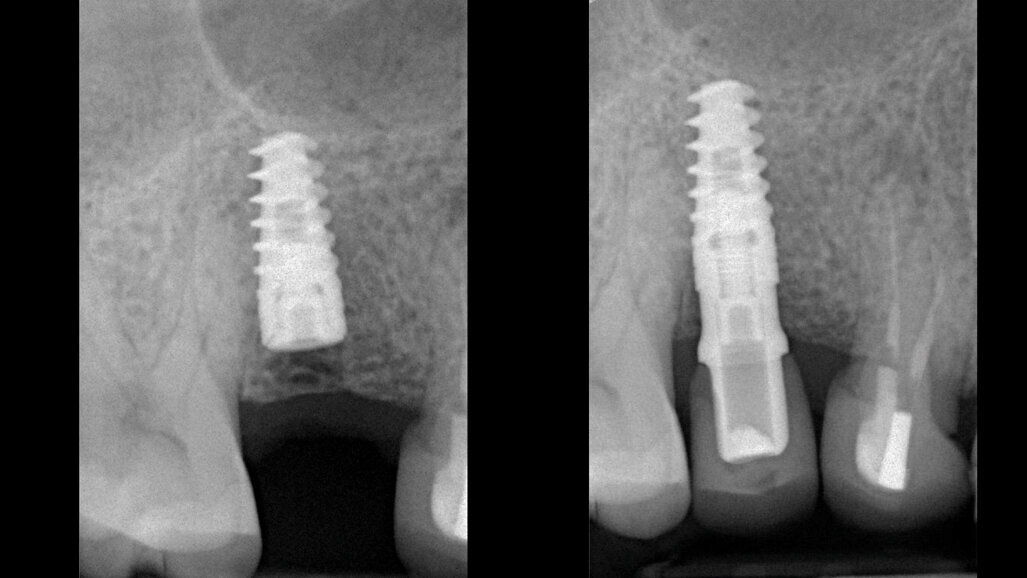

Obr. 8: RTG snímek pořízený bezprostředně po zákroku. Obr. 9: RTG snímek pořízený po osmi měsících zatížení.

Celkový klinický čas potřebný pro preparaci osteotomie byl zhruba 7 minut. Implantát měl v době zavedení vysokou hodnotu primární stability: hodnota ISQ naměřená v bukolingválním směru byla 84 a hodnota naměřená v meziodistálním směru byla 81. Nahlášená číselná hodnota týkající se pooperační bolesti byla 1. Ve druhé fázi implantologického ošetření, která byla provedena po 40 dnech, byly zjištěny nové hodnoty ISQ, a to bukolingválně 84 a meziodistálně 82. Po třech měsících se tyto hodnoty ještě zvýšily na 86 bukolingválně a 84 meziodistálně. Kontrolní RTG snímek pořízený po osmi měsících zatížení ukazoval na úplnou oseointegraci implantátu s velmi dobrým zhojením kosti kolem krčku abutmentu (obr. 9).